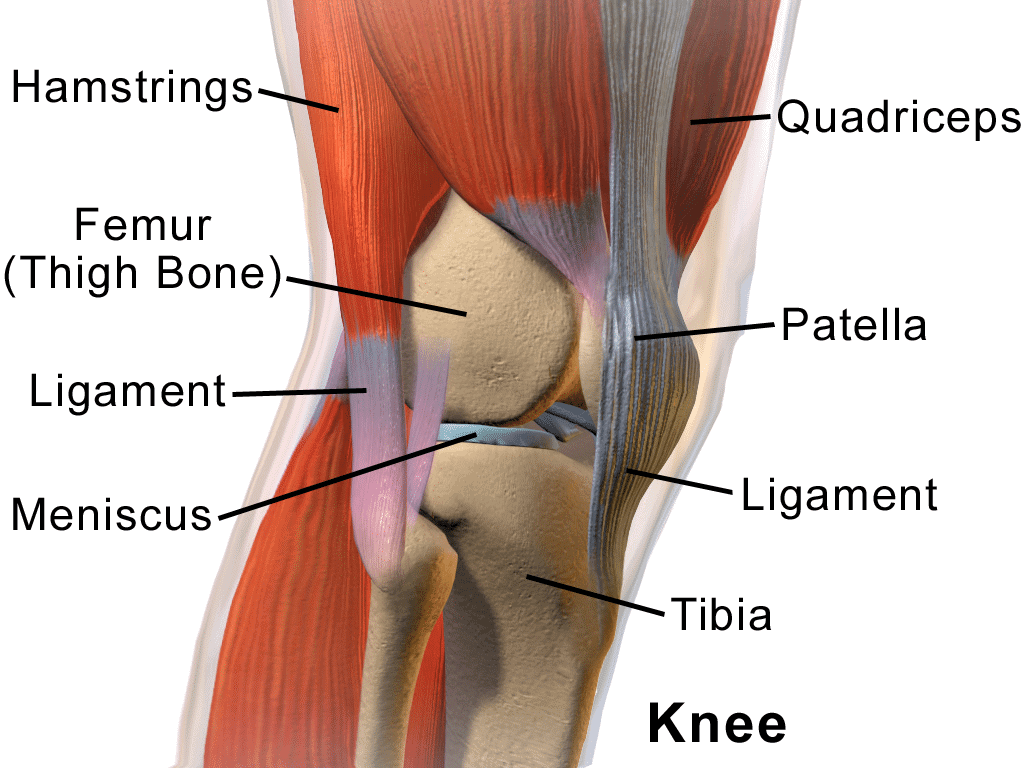

Basic facts about the structure of the knee

• Due to the many bones, cartilage, and ligaments that support it, the knee is the largest joint located in the human body.

• The patella or knee bone is composed of tendons, cartilage, bones, and ligaments.

• The three bones that join each other to form the knee are the tibia (shinbone), the femur (the thighbone), and the patella (kneecap).

• Articular cartilage is the slippery substance that covers the tips or ends of the tibia and femur, as well as the back of the patella. This material helps all the knee bones move smoothly against each other as you walk, jump, or otherwise move about on your legs.

• The ligaments are the parts of the body that connect our bones to other bones. They operate in that same manner within the knee joint.

• The meniscus. We each have one of these “wedge-shaped” pieces of cartilage in each knee to provide us with “shock absorption” as we walk around, jog, play basketball or otherwise place heavy burdens on our knees.